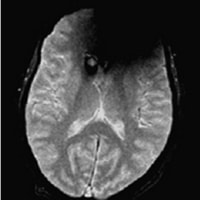

患者様を案内又は搬送する際は、患者様の金属の有無について十分注意をお願いします。金属が体内に入っている方や、 身につけている方は写真上に影響が出ると同時に体内金属が動いたり、発熱したりする場合があり危険な場合があります。 金属があった場合の症例を提示します。

ヘアピンによる影響